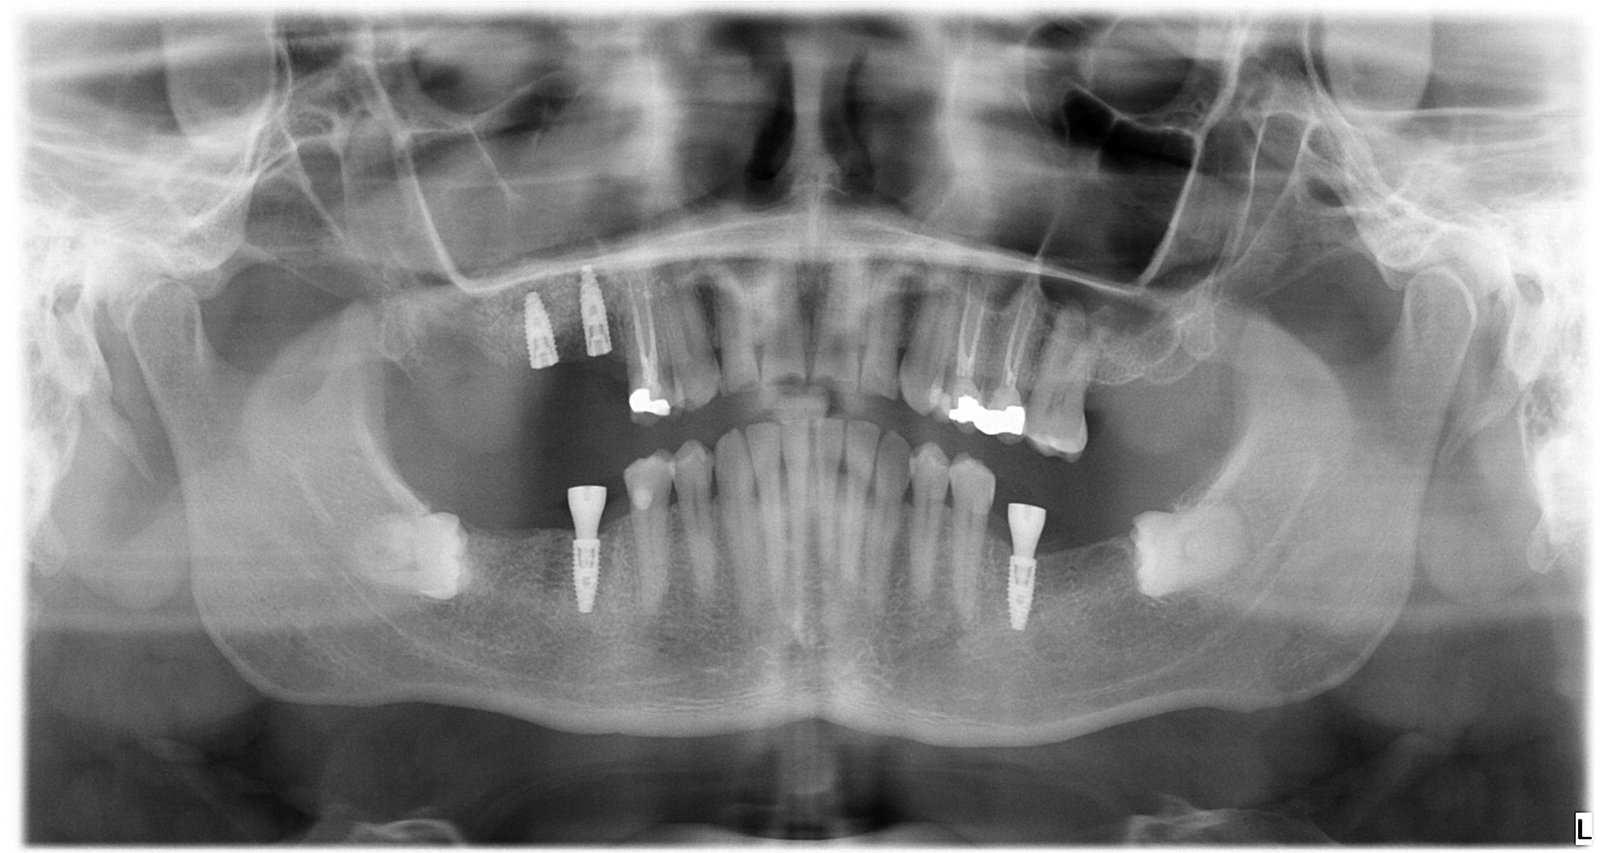

Caso 2 - caso de Carga inmediata

Buscaba una solución rápida y eficaz para volver a masticar y sonreír con normalidad. Mediante carga inmediata conseguimos rehabilitar su boca en una sola intervención, combinando rapidez, estética y funcionalidad.

Se confirma la correcta posición y fijación de los implantes, lo que permite colocar una prótesis fija inmediata con total fiabilidad.